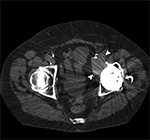

In the case of infection, which is uncommon, nuclear medicine studies, aspiration or biopsy may be required to confirm the diagnosis. Small-particle disease results from implant wear, leading to particle shedding and provocation of a histiocytic response, which manifests as bone destruction. The most common cause of small-particle disease is polyethylene wear, and most patients remain asymptomatic until extensive bone loss is present (Ohashi, 2009; Naudie, 2004). Radiographic evaluation of small-particle disease can be limited by location of the lesion, position of the hardware, and patient body habitus. In particular, evaluation of peri-acetabular particle disease can be challenging due to the above factors. In such cases, CT may be indicated to determine the presence and volume of osteolysis prior to hardware revision (Figure 12) (Chiang, 2003; Claus, 2004).

Small Particle Disease. Axial CT image of the pelvis demonstrates left total hip arthroplasty with adjacent cortical disruption (curved arrow) and destructive soft tissue lesion (arrowheads) arising from the anteromedial aspect of the acetabulum, consistent with small particle disease due to polyethylene wear.